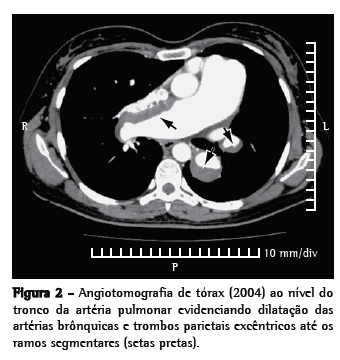

Em abril de 2004, apresentou piora funcional progressiva, chegando à classe funcional IV. A angiotomografia de tórax evidenciou trombos parietais excêntricos, de predomínio no tronco da artéria pulmonar (dos ramos principais até os ramos sub-segmentares, bilateralmente), com calcificações periféricas aos trombos (Figura 2). Apresentava ainda padrão de perfusão em mosaico no parênquima pulmonar e dilatação de artérias brônquicas. A investigação para trombose venosa profunda e trombofilias resultou negativa. Apesar da piora de classe funcional, a distância percorrida no teste de caminhada de seis minutos (TC6)-usado para avaliar a capacidade funcional-foi de 414 m; dissociação essa já descrita para pacientes com HAPI.(7) A paciente permaneceu todo o período de tratamento adequadamente anticoagulada. As imagens tomográficas eram totalmente compatíveis com o diagnóstico de HPTEPC. Felizmente, o conhecimento do diagnóstico prévio da paciente (HAPI) nos permitiu optar pelo tratamento clínico, com o uso de sildenafila 75 mg/dia. Houve ótima resposta clínica e retorno, após algumas semanas, à classe funcional II.